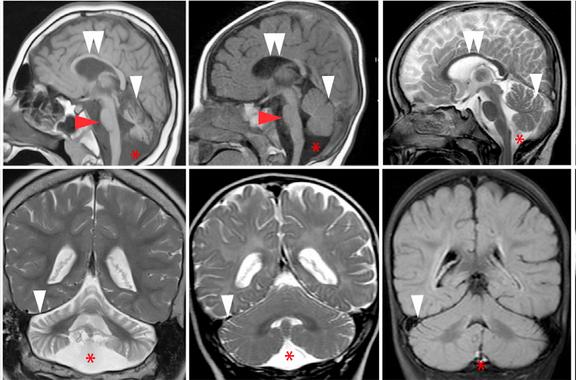

Descubren un nuevo trastorno neurológico en niños del este de Turquía 25/04/2014Dos equipos de investigación han descubierto, de forma independiente, una enfermedad neurodegenerativa desconocida hasta ahora y que por ahora solo se ha detectado en el este de Turquía. Quienes la padecen tienen un cerebro más pequeño de lo normal, además de defectos sensoriales y motores. La malformación está causada por una única mutación de un ancestro común nacido en el antiguo Imperio otomano hace 16 generaciones. Las causas genéticas de esta rara enfermedad se han descubierto gracias al análisis del ADN de varios niños turcos con trastornos neurológicos. Uno de los dos trabajos, liderado por el Instituto de Biotecnología Molecular de la Academia austriaca de Ciencias (IMBA), describe cómo este nuevo trastorno está producido por una mutación en el gen CLP1. "Nosotros estábamos trabajando con modelos de ratón con mutaciones que provocaban la degeneración de sus neuronas motoras", explica el argentino Javier Martínez, del IMBA, desde Viena. "En un congreso, mi equipo conoció al del Baylor College of Medicine (Houston, EE.UU.), que hablaba del caso de once niños turcos con una enfermedad neurológica no diagnosticada que presentaban el mismo patrón". A partir de ese momento, los dos grupos decidieron colaborar para entender qué les sucedía a aquellos chicos. Analizando el ADN de miles de niños turcos, encontraron que cuatro de las 2.000 familias estudiadas, que en principio no estaban genéticamente relacionadas, poseían la misma mutación, lo cual indica la existencia de una mutación ancestral. "El problema está en el alto grado de consanguinidad que hay en estas regiones", explica Martínez. Más información SINC